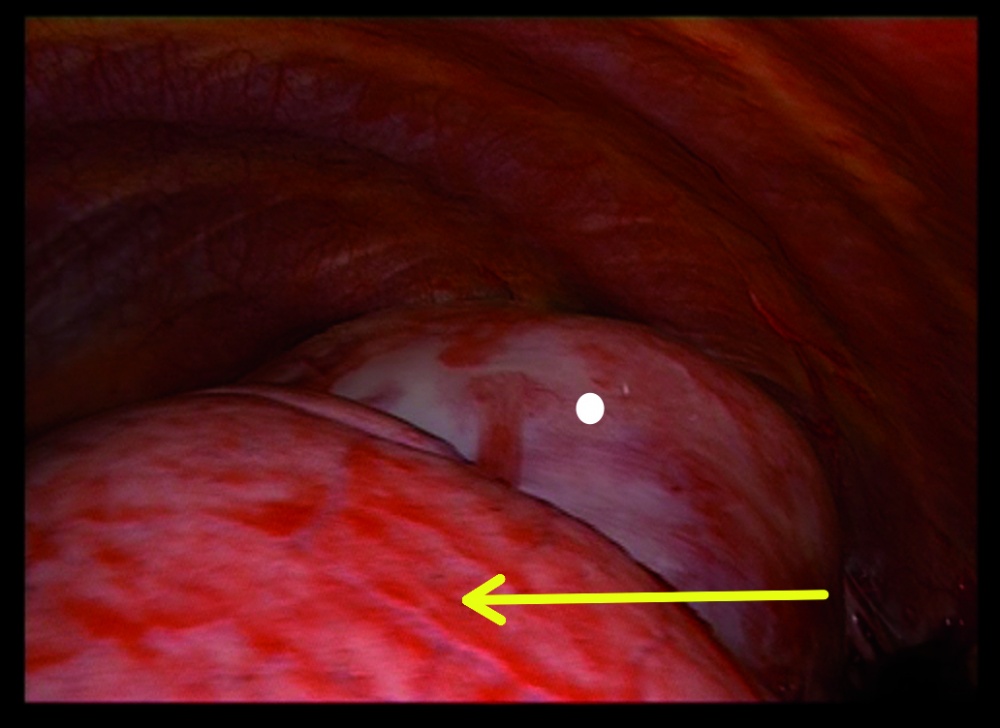

Zwei Tage nach Aufnahme zeigte der Patient einen starken Hämoglobinabfall von 12,4 g/dl auf 7,9 g/dl, so dass eine notfallmäßige Thorakoskopie zur Blutstillung und Histologiegewinnung durchgeführt werden musste. Auf eine erneute Bildgebung präoperativ wurde hierbei aufgrund eines symptomatischen Patienten mit Kurzatmigkeit und niedrigem Hämoglobinwert verzichtet. Bei dem Eingriff bestätigte sich der initiale Verdacht eines Hämatothorax. Es konnten 1,5 l teils frischen, teils mit Koageln durchsetzten Blutes abgesaugt werden. Es zeigte sich links apikal ein von der dorsalen Thoraxwand ausgehender und dort adhärenter Tumor mit erkennbarem Tumorstiel, von welchem die Blutung ausging. Aufgrund der thorakoskopisch schlechten Zugänglichkeit der Blutung und der Kontaktfläche zur Thoraxwand wurde eine Thorakotomie durchgeführt, die Blutung gestillt und der Tumor in toto entfernt.

Bei der Thorakoskopie zeigte sich die Lunge makroskopisch unauffällig und nur durch kleinere Adhäsionen im Bereich des Oberlappens mit dem Tumor verbunden. Der Tumor selbst war solide, von einer Kapsel umgeben, bindegewebig und apikal dorsal an der Thoraxwand adhärent. Hinter dem Tumor bestand weiterhin eine Blutung, die thorakoskopisch nicht erreicht werden konnte; daher erfolgte der Entschluss zur Thorakotomie. Ob er ursprünglich von der Lunge oder der Thoraxwand ausging, ließ sich intraoperativ nicht mit letzter Sicherheit klären.